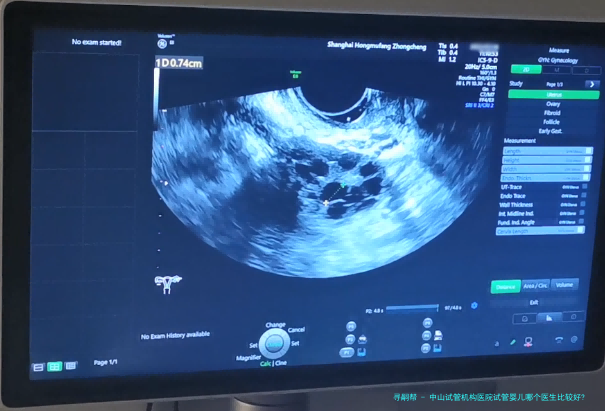

胚胎培养:将促排卵后的卵子和精子在实验室进行受精和培养,待胚胎发育到5-8个细胞期后进行移植评估。 宫颈检查:使用超声刀对宫颈进行观察和检查,确保宫颈健康状况良好。 胚胎移植:将优质胚胎经阴道或子宫腔内种植到女性子宫内。 移植后恢复期:患者需保持充分休息,避免剧烈运动和性生活,并接受药物治疗以提高妊娠成功率。中山试管机构医院凭仗雄厚的医疗力量、先进设备和专业的医护团体,专心于为每一位病患提供优质的试管婴儿服务。要是您正进行考虑寻求试管婴儿治疗,建议您咨询中山试管机构医院相关专业人士,取得更详细的信息和个性化的方案。